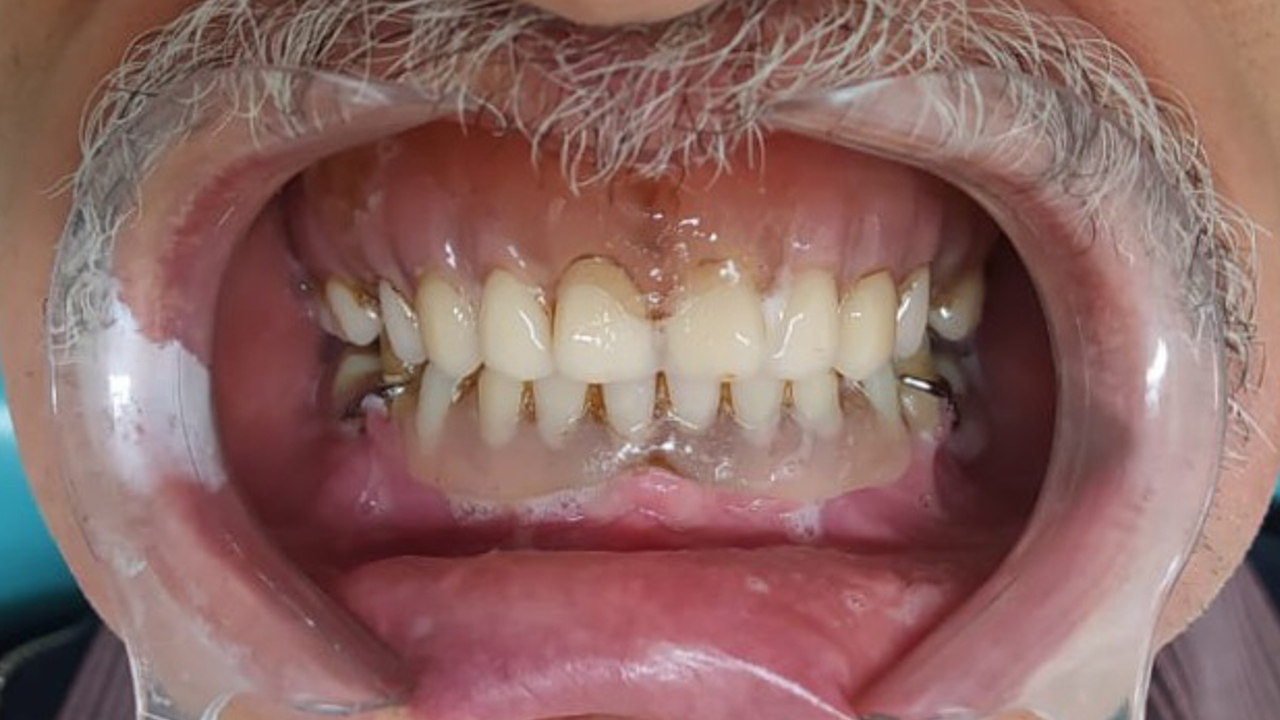

O implante ficará no lugar da raiz do dente que foi extraída, e é nele que será instalado o dente artificial (coroa). Para uma correta indicação, é necessário um ótimo planejamento!

PROTOCOLO é um tipo de prótese que fica presa por implantes, substituindo a dentadura móvel. Ou seja, DISPENSA o uso de pastas ou adesivos fixadores. Só o dentista consegue por e tirar a prótese da sua boca!😷 Além disso, o PROTOCOLO, melhora a mastigação e a fala,

melhorando a qualidade de VIDA dos pacientes.